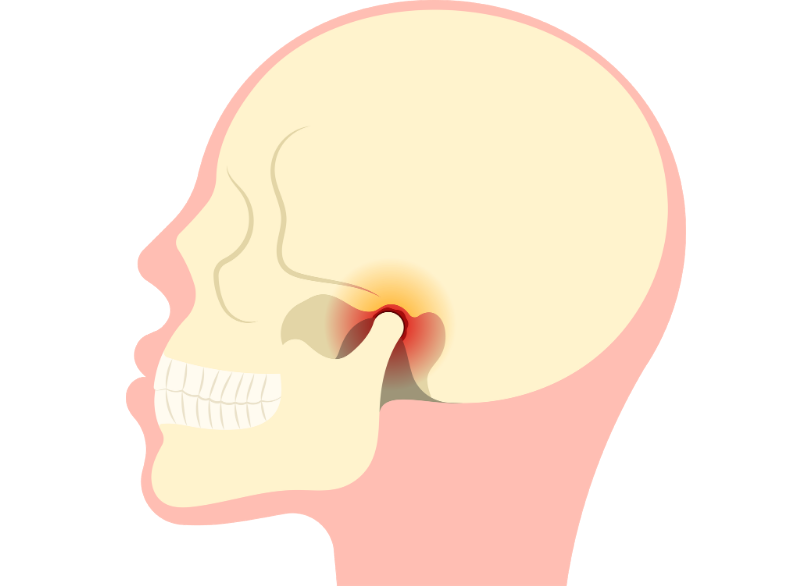

顎関節症の治療

顎の痛み・音・開けにくさを改善する

「口を開けると顎が痛い」

「口を開閉するとカクカク、ジャリジャリと音がする」

「口が指2本分くらいしか開かない」

これらの症状がある場合、「顎関節症(がくかんせつしょう)」の疑いがあります。

顎関節症は噛み合わせの異常、ストレスによる食いしばり、姿勢の悪さ、外傷など、複数の要因が絡み合って発症します。

放置すると食事や会話が困難になるだけでなく、頭痛や肩こり、めまいなど全身の不調につながることもあります。